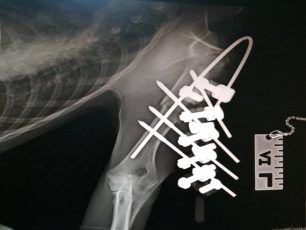

Στο κτηνιατρείο του Αλέξανδρου Υφαντή στη Λευκάδα χειρουργήθηκε, αρχικά για την αποκατάσταση του σπασμένου ποδιού του, το σκυλί που ξυλοκοπήθηκε άγρια από τον ιδιοκτήτη του στις 13 Μαρτίου στο Λαδοχώρι Θεσπρωτίας. Ο δράστης πλάκωσε τον…διαβάστε περισσότερα